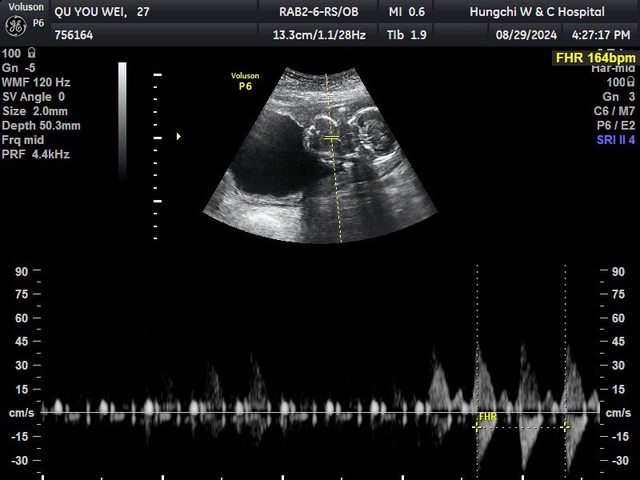

以我虛弱的體質加上懷孕

老公半信半疑,後面醫生跟我說是女孩

巧克力囊腫+多囊+經期不規則+宮寒

我很開心現在身體裡有個小寶貝

https://i.imgur.com/lEm2Spn.jpeg